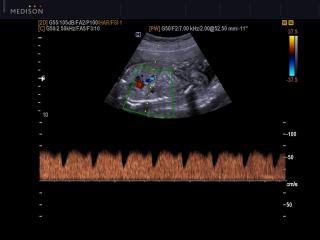

- PW - импульсно-волновой допплер, steering - изменение допплеровского угла в режимах CD и PD, автоматический анализ допплеровских кривых.